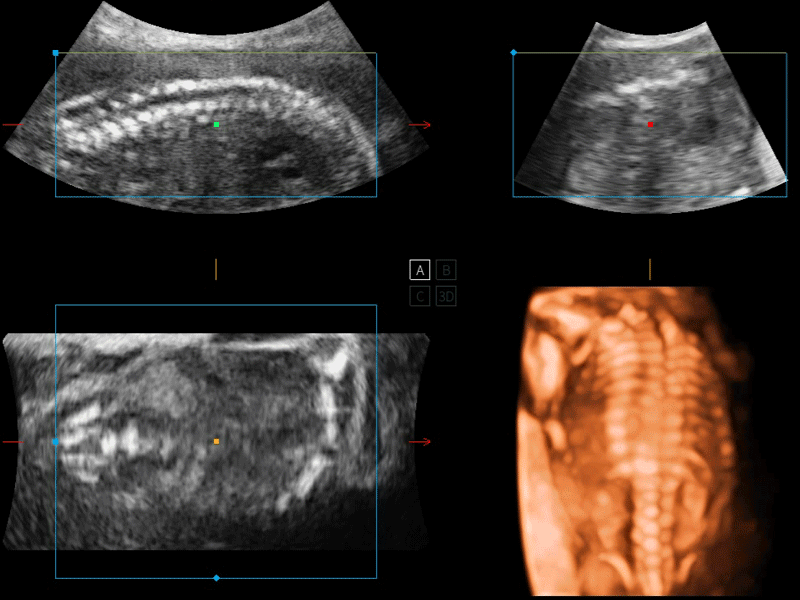

S-Fetus 产科扫查助手

S-Fetus基于大数据深度学习算法,能够帮助您在产前筛查过程中智能识别胎儿标准切面、自动测量并录入报告。一个按键,即可智能、精准、高效地获取胎儿生理指标,极大简化您的产科检查操作。

S-Live 高分辨率容积成像

通过仿真成像技术对3D/4D立体数据进行渲染,多种初始光源位置可选,并支持轨迹球360°光源位置自由调节,清晰显示不同方位容积图像细节。